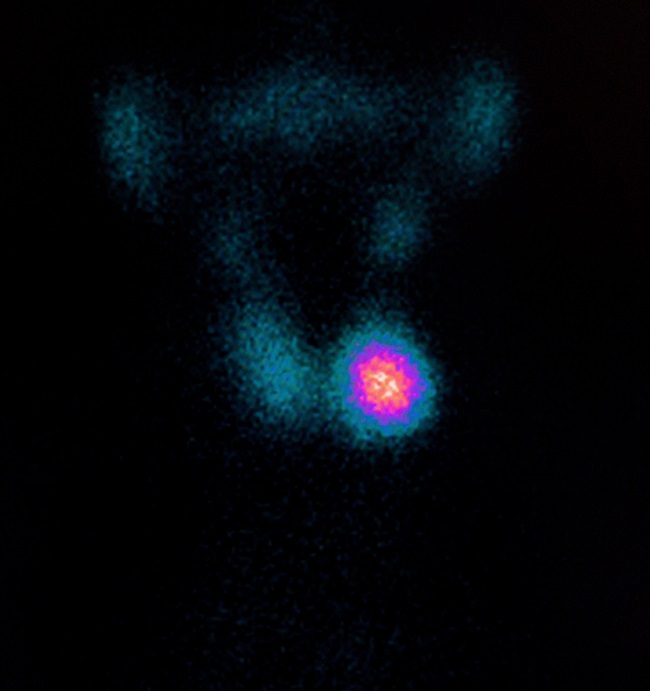

Gambar 3. Nodul Tiroid Dingin

Kanker tiroid hampir selalu dijumpai sebagai nodul tiroid hipofungsi atau nodul dingin, walaupun 80–90% dari seluruh nodul dingin bersifat jinak. Karena nilai spesifisitas yang rendah, bila ditemukan nodul dingin harus dilakukan evaluasi lanjut dengan USG tiroid.[6–8]

Pemeriksaan USG tiroid memang dapat menilai karakter nodul tiroid dan risiko keganasannya melalui klasifikasi thyroid imaging and data reporting system (TIRADS). Akan tetapi, TIRADS tidak memasukkan kriteria status fungsional nodul tiroid, walaupun nodul tiroid panas memiliki nilai prediktif negatif keganasan sebesar 96–99%.[6–8,11]